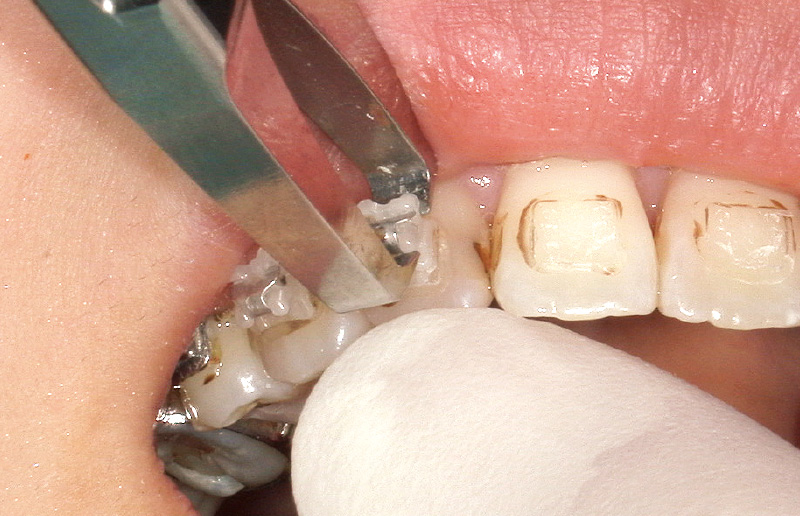

「ボンドフィルSBⅡ」の除去には、CA用カーバイドバーを使用し、その後シリコンポイントで研磨を行う(図15A, B)。バーの形状上エナメル質が削れにくいため、ルーペ視野下で操作を行えば歯質の切削量を最小限に抑えられる。一方、CR系矯正用接着材の場合はレジンが硬いため、ダイヤモンドバーやカーボランダムポイントなどを用いた削合が必要となる。その際には健全なエナメル質を損傷しないようルーペを用いて細心の注意を払った操作が求められる。このように、接着材それぞれの特性を正しく理解し適切に活用することで、デボンド時の患者への負担を軽減しつつ、治療効率や患者満足度の向上にもつながると考える。

図15A, B 「ボンドフィルSBⅡ」除去の流れ

A:「スーパーボンド」や「ボンドフィルSBⅡ」は熱で軟化する性質があるため、弱い圧で効率的に除去可能である。

B:シリコンポイント(茶)で研磨